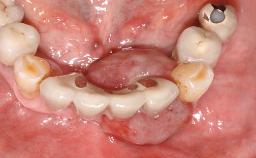

Surgical treatment of a 67-year-old male patient exhibiting an extended edentulous space in the anterior maxilla after the removal of three hopeless incisor teeth.

The video demonstrates implant placement using a surgical stent according to the principle of prosthodontically driven implant placement. The deficient ridge is augmented with locally harvested autologous bone chips, a superficial layer of xenogenic DBBM particles and a resorbable collagen membrane. The surgery is completed with a precise, tension-free primary wound closure.

The case concludes with the presentation of the final prosthesis and the esthetic outcome, demonstrating stable soft tissue conditions and stable bone crest levels at the 3-year follow-up.